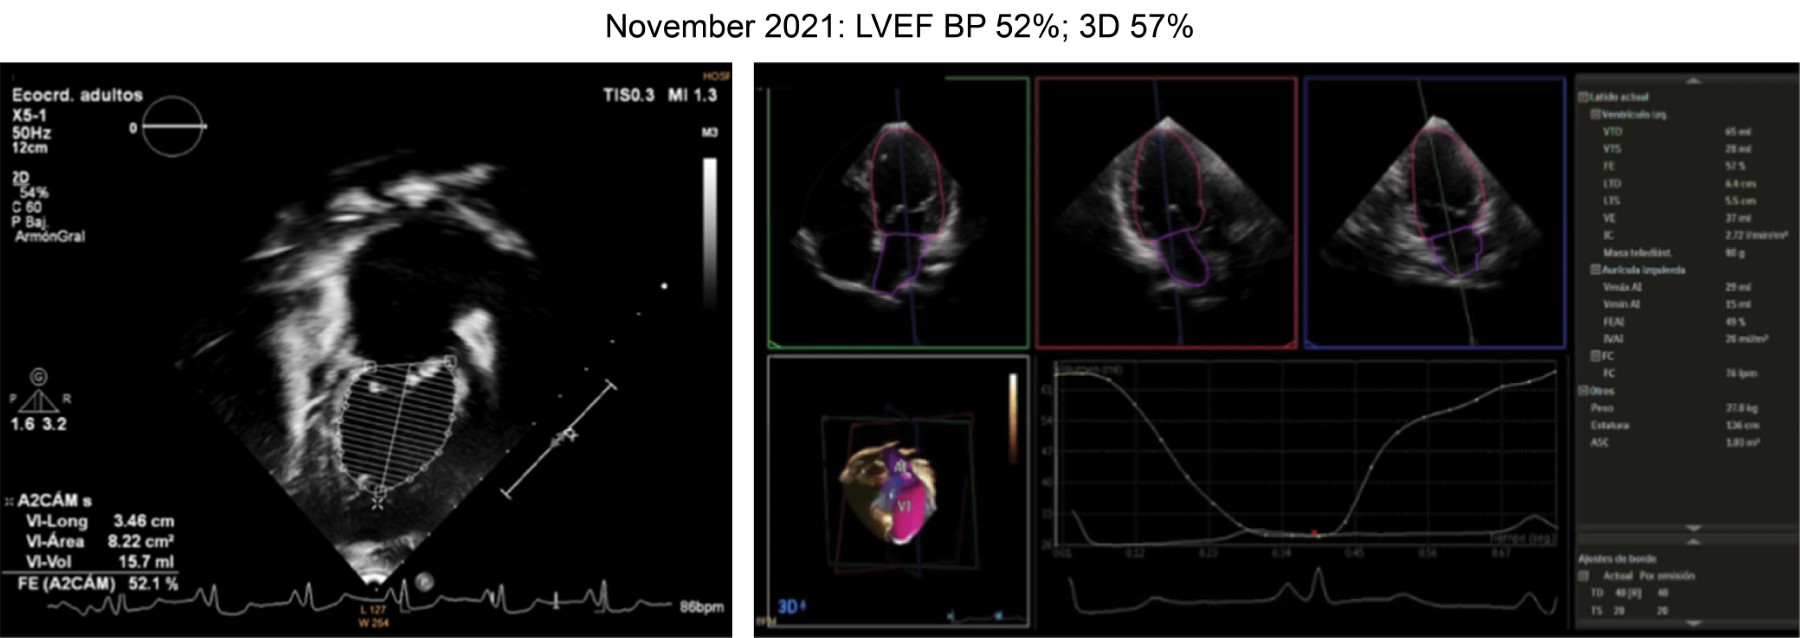

At two years of age, she was readmitted to the hospital due to decompensation of heart failure. Echocardiography revealed dilated cardiomyopathy, mild mitral insufficiency, and dilated left ventricle. MV E/A ratio > 200 mmHg, biplane LVEF 38%, synchrony index 36%, delayed septal contraction in relation to the free wall of 88 ms and 53 ms, RVP 38 mmHg. It was decided to perform pulmonary artery banding. She was discharged after nine days of the procedure due to improvement (Figure 1).

At the age of six years, a new echocardiogram was performed, revealing mild tricuspid regurgitation, mild mitral regurgitation, preserved systolic and diastolic function of the right ventricle, preserved diastolic function of the left ventricle, systolic dysfunction of the left ventricle, and a global strain of -10. The patient continues to be monitored in Cardiology.